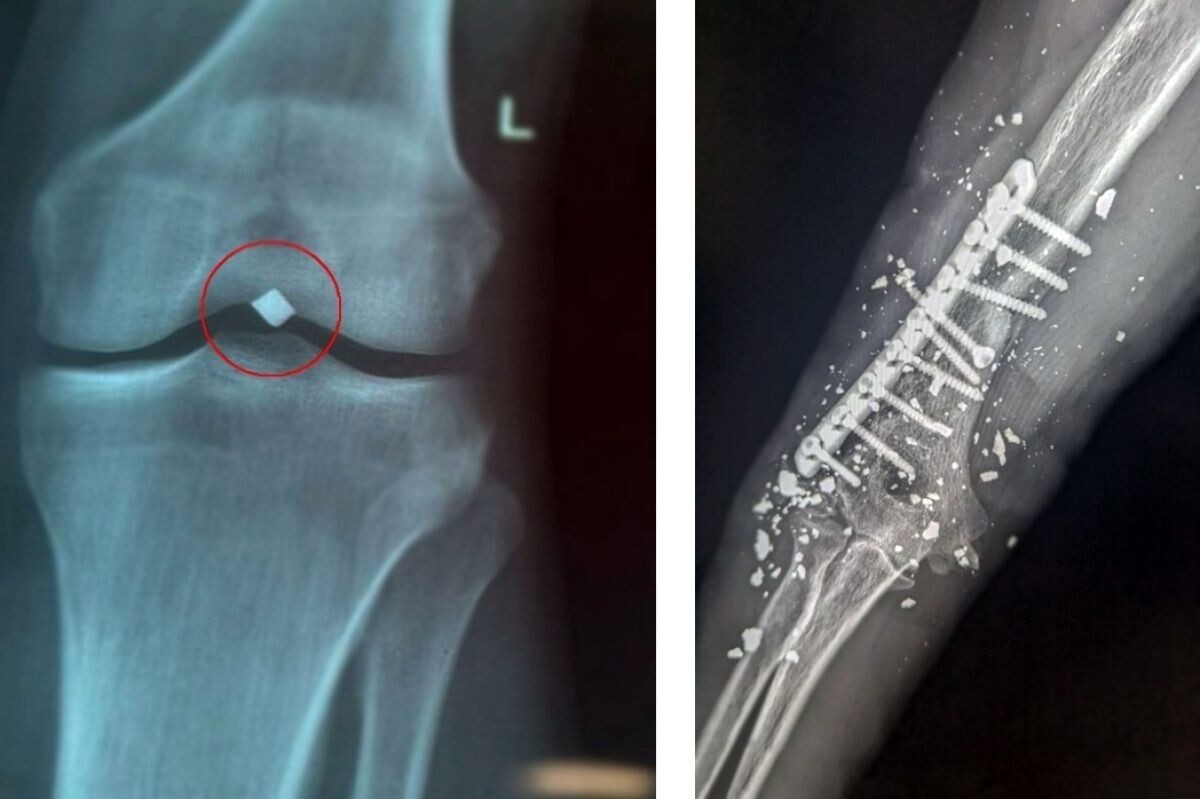

Второй пациент поступил в ОКБ с тяжелой травмой правого плеча, полученной в результате минно-взрывного ранения в ноябре 2024 года.

Сразу же после травмы мужчине провели экстренную операцию — первичную обработку раны и накостный остеосинтез плечевой кости. Однако возникли осложнения: появились симптомы повреждения лучевого нерва и началось нагноение вокруг имплантированной металлической конструкции. В течение проводимого лечения ситуация осложнилась формированием хронического свища с постоянным выделением гноя в области фиксации металла. Пациента мучили сильные боли. Сильные боли.

Результаты исследования подтвердили наличие глубокого воспалительного процесса, связанного непосредственно с установленной ранее конструкцией.

Врачи приняли нестандартное решение: использовать комбинированный метод оперативного вмешательства, который позволил аккуратно удалить всю конструкцию, сохранив целостность нервных структур и избежав повреждения лучевого нерва.

Операция прошла успешно, без осложнений, сохранена двигательная активность руки и чувствительность кисти.